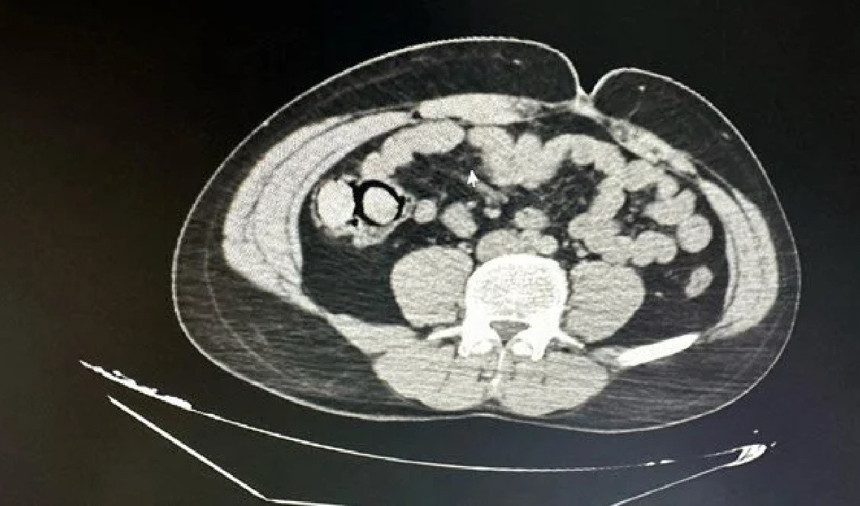

Şüphelilerin hastanede yapılan muayenesinde, midelerinde 10 parça halinde 113 gram metamfetamin tespit edildi.